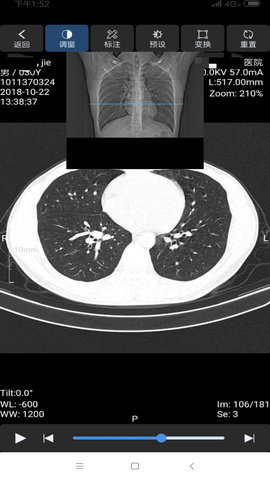

飞图影像是一款让医生在手机上处理医疗工作的软件,医生可以随时查看医疗影像,还能与其他同行讨论病例细节。软件让医生在查房间隙或外出时快速调取患者CT图像,直接标注病灶区域并生成诊断意见。解决了传统工作站固定位置的限制,急诊科医生接到紧急会诊通知后,用手机就能立即查阅影像资料。临床教学时,主治医师可以通过软件实时共享影像资料给实习医生,用手指在屏幕上标注关键解剖结构。

1、影像浏览界面提供窗宽窗位调节功能,可根据诊断需求优化图像显示效果。

1、测量工具支持在影像上标注病灶尺寸,自动计算长宽比例和病灶面积。

2、打开CT序列时双指捏合调整图像层厚,长按屏幕激活测量工具栏。

3、在冠状位视图下点击标注按钮,用红色圆圈标记可疑结节区域。

4、选择多平面重建模式,浏览横断位、矢状位和冠状位三个视图。